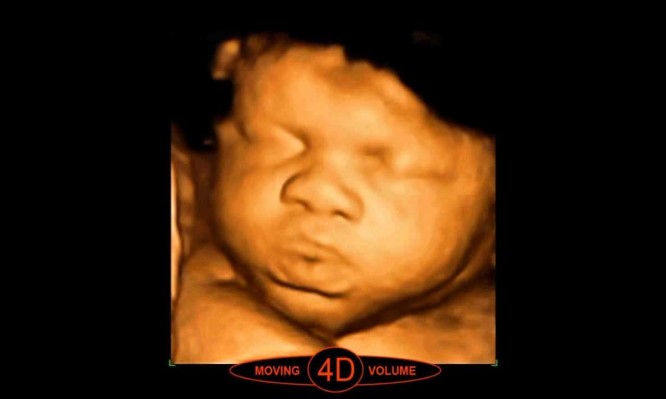

Πως φαίνεται το μωρό με υπερήχους 2 3 και 4 διαστάσεων. ΒΙΝΤΕΟ

Στο βίντεο που θα παρακολουθήσετε θα δείτε πως φαίνεται ένα μωρό μέσα στην κοιλιά της μητέρας του, με υπερήχους δυο, τριών και (πλέον) τεσσάρων διαστάσεων. Μέχρι τις αρχές της δεκαετίας του 70 δεν υπήρχαν καν τα μέσα να δει κάποιος το μωρό μέσα από την κοιλιά. Αργότερα και όσο η τεχνολογία εξελισσόταν έγιναν οι υπέρηχοι 2d (2 διαστάσεων) και ο γιατρός μπορούσε να δει το μωρό. Στη συνέχεια η εξέλιξη έκανε τους υπερήχους τρισδιάστατους (3d), όπου πια και τα χαρακτηριστικά είναι εμφανέστατα και πρόσφατα περάσαμε στην τέταρτη διάσταση όπου είναι σαν να παρακολουθούμε απλά ένα βίντεο. Τόσο ζωντανά.

Στην αρχή του βίντεο βλέπουμε την απεικόνιση των δύο διαστάσεων, μετά των τριών και φτάνουμε στις 4.